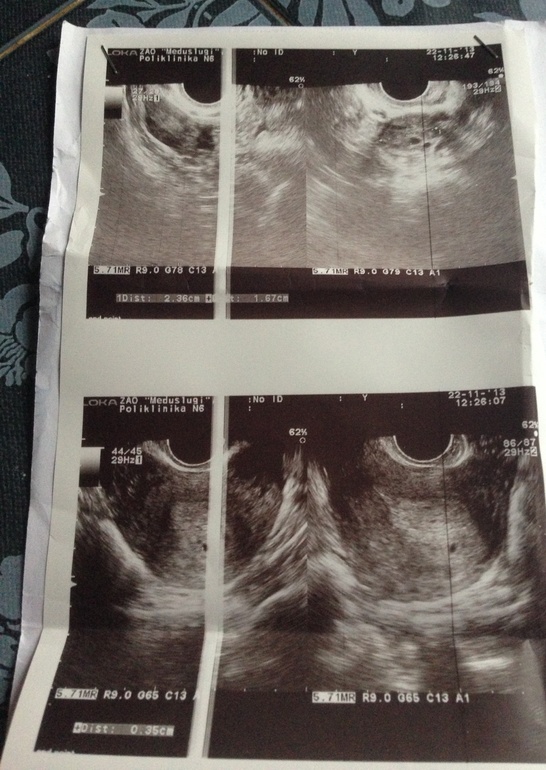

Не выдержала пошла на узи . Задержка 8 дней

УЗИ, КТГ, доплерВ полости. Матки определяется одно плодное яйцо 3 мм)))) это уже радость !

Эндометрий размером 24мм неоднородный с мелкими участками раздражения .

Левый яичник с желтым телом 23*16 мм

Беременность малого срока, приблизительно 2-3 нед . Сказали быть 12-13 декабря сердце послушаем . Вот так , вроде все нормально )

Неа, хгч вчера было 992) увидели вагинально еще очень мал , но по моим подсчетам все совпадает , ))